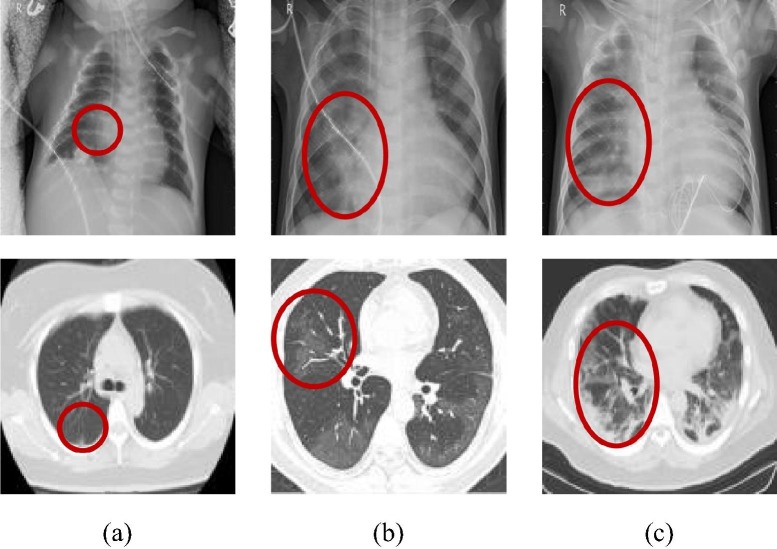

2.2.1. Acquisition of the mixed dataset

The imaging features of X-ray and CT images will change with the severity and duration of infection [35], [36], as shown in Fig. 4 . In general, the lesions of early COVID-19 patients mostly occur at the bottom of the lung and below the pleura, mainly in the peripheral zone of the lung. It may present as a single or double lung multiple patchy ground-glass shadows, sometimes accompanied by a slight bronchial inflation sign, as shown in Fig. 4(a) [37], [38]. With the further progress of the lesion, consolidation changes may occur. The scope and types of inflammatory lesions increase, which can begin to spread to multiple lung lobes. At this time, the patient's images show a mixture of ground glass shadow and solid change shadow. Besides, some patients will also have mild cord shadow and a small amount of pleural effusion, as shown in Fig. 4(b) [39], [40]. Severe novel coronavirus pneumonia patients have larger lesion regions and diffuse interstitial changes will appear. The symptoms of the white lung will appear at the later stage, often accompanied by a solid change shadow, which will always endanger the patient's life and health, as shown in Fig. 4(c) [41].

Fig. 4.

Imaging features of COVID-19 in different periods. (The first row is the X-ray images and the second one is the CT images. The red region indicates the position of the COVID-19 signs.) (a) early stage; (b) middle stage; (c) later stage.